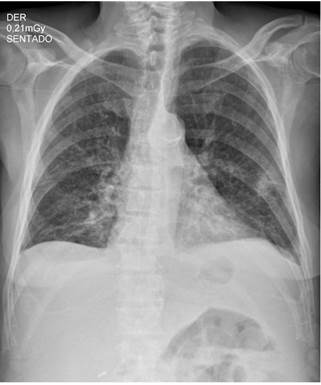

Ingresó por un cuadro clínico de 9 meses de evolución consistente en pérdida de peso de aproximadamente 12 kg, sudoración nocturna, astenia, adinamia y tos ocasionalmente productiva en el último mes. Adicionalmente, manifestó tener deposiciones diarreicas sin moco ni sangre, aproximadamente de 4 a 5 deposiciones al día durante 4 días antes del ingreso, la cual resolvió por sí mismo con hidratación y medidas generales. Al ingreso se documentó fiebre en 38,3 °C, palidez generalizada y taquicardia; y los exámenes de laboratorio iniciales documentaron leucopenia, anemia de volúmenes bajos en criterios de transfusión, trombocitopenia, hiponatremia leve hipovolémica hipoosmolar, hipomagnesemia e hipoalbuminemia (Figura 1 y Tabla 1). En el estudio de tomografía de tórax se obtuvieron hallazgos compatibles con silicoantracosis e imágenes hipodensas en las vértebras de carácter inespecífico (Figura 2).

Figura 1 Radiografía anteroposterior (AP) de tórax que muestra opacidades intersticiales reticulares gruesas en ambos campos pulmonares y ángulos costofrénicos libres.